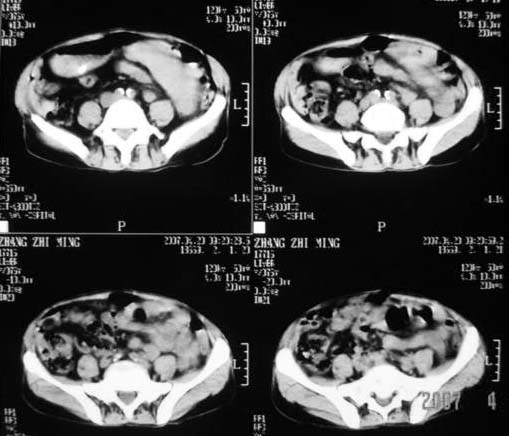

以下是引用dyqct在2007-4-20 16:38:00的发言:[br]考虑:1、巨脾;[br] 2、肝内多发低密度,首先考虑转移瘤;[br] 3、胆囊多发结石。

以下是引用andymaomao在2007-4-20 16:47:00的发言:[br]肝脾增大,肝内胆管扩张,且可见多发小囊性低密度灶,胆囊窝区高密度影,手术化疗病史,贫血....[br]1.肝脾大及贫血与术后化、药疗有关;[br]2.胆囊窝区高密度影,术后改变?肝内胆管扩张,积液?[br]3.肝内多发低密度灶,性质?建交增强